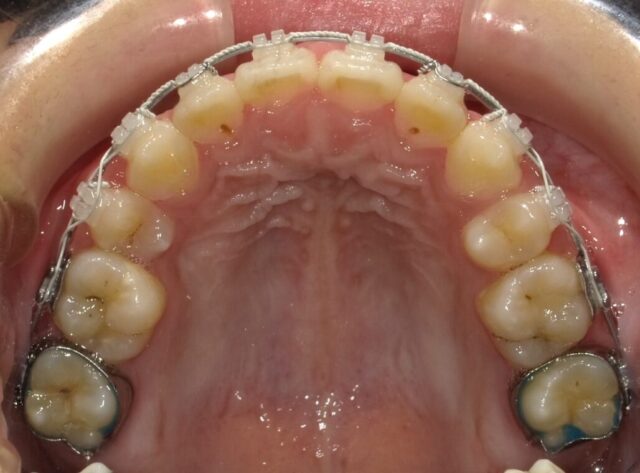

≪上顎咬合面観≫

2023年5月

2025年1月